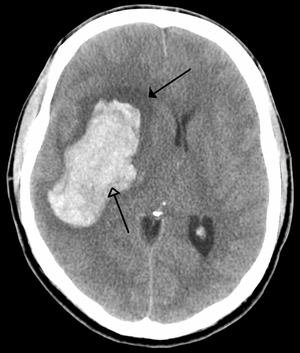

CT scan slice of the brain showing a right-hemispheric ischemic stroke (الجانب الأيسر من الصورة).

An intraparenchymal bleed (bottom arrow) with surrounding edema (top arrow)